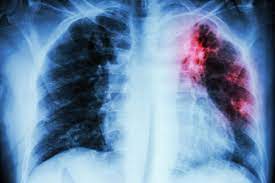

Argentina tiene la segunda tasa de mortalidad por cáncer de mama (CM) más alta de América del Sur. La incidencia estandarizada por edad de cáncer de mama en Argentina es de 73 por 100.000. A pesar de la disponibilidad de servicios de detección temprana, el 30% de los CM se diagnostican en estadios avanzados de la enfermedad. Se describe el "Estudio de la encuesta Tiempo 1". El tiempo 1 se define como el tiempo desde la primera aparición de signos o síntomas de CM hasta la primera consulta dentro del sistema público de salud J Cancer Educ. 2021

Supervivencia en el mundo real: análisis nacional de pacientes tratadas por cáncer de mama en estadio temprano

Más de la mitad de los pacientes estaban infrarrepresentados o no estaban representados en los ensayos clínicos debido a la edad, la comorbilidad o la raza. Algunos de estos grupos experimentaron una supervivencia más pobre en comparación con los que estaban bien representados en los ensayos. Los investigadores deben asegurarse de que los participantes del estudio reflejen la población de la enfermedad para respaldar la toma de decisiones basada en evidencia para todas las personas con cáncer. JCO Oncology Practice,24 de septiembre de 2021